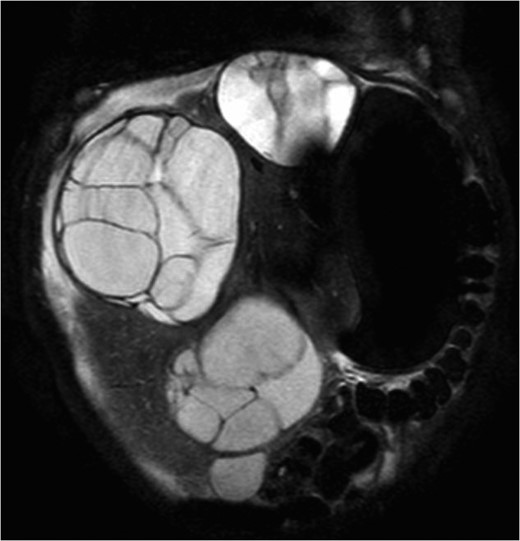

A 13-month-old male with BWS and Kleinfelter Syndrome was referred to our institution for evaluation of asymptomatic liver masses. Hepatic workup completed at both 4 and 7 months of age showed normal liver function tests, but elevated alpha-fetoprotein (AFP) levels with a maximum of 167 000 ng/mL. MRI of the abdomen revealed six multi-locular cystic hepatic masses, ranging from 3.8 to 8.9 cm in maximal diameter, with corresponding hepatomegaly (19 cm) and significant intra-abdominal mass effect causing displacement of the proximal duodenum and proximal pancreas to the left of midline (Fig. 1). These imaging findings were consistent with the diagnosis of MLH.

Coronal T2 abdominal MRI demonstrating multiple, large, multi-loculated cystic hepatic masses and significant hepatomegaly.